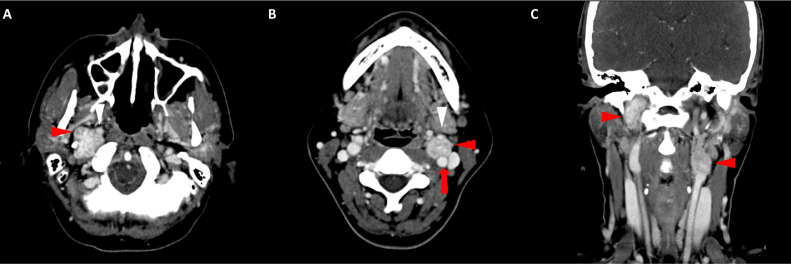

Fig. 3

圖 3:多個(gè)胃腸道間質(zhì)瘤的冠狀和矢狀圖像。 (A 和 B)冠狀動脈相對比增強(qiáng) CT 圖像顯示胃賁門產(chǎn)生的外生性腫塊。 (C 和 D)矢狀動脈相位對比增強(qiáng)圖像顯示腫塊的異質(zhì)性和外生結(jié)構(gòu)。